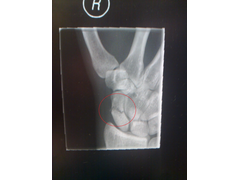

wrist:

wrist

the worst bit is I can't drive for at least 6 weeks

No crutches for me - the wrist and ankle are both on the right side....